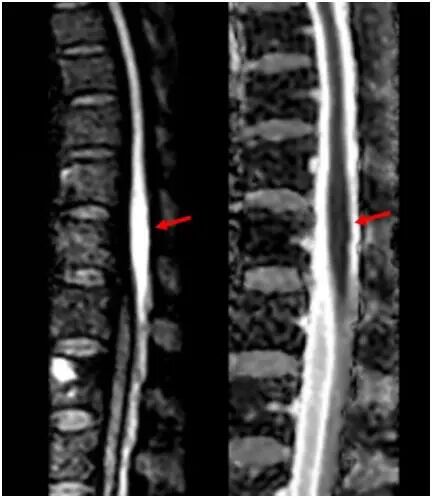

神经内科团队接诊后,凭借丰富临床经验,高度怀疑脊髓梗死。患者住院第2天早上,双下肢剧烈疼痛,很快完全瘫痪。主管护师逯红专查看患者后呼叫卒中救治团队。神经内科副主任医师刘效辉判断患者腰段脊髓再次梗死,科室迅速启动院内卒中绿色通道。医学影像科技师李峥根据神经系统查体确定的病变位置,调整扫描参数后对患者完善相关检查,磁共振影像结果显示患者脊髓圆锥存在弥散受限异常信号。医学影像科主任医师修建军阅片,确诊为脊髓梗死。超声医学科副主任医师包守刚进行超声检查排除主动脉夹层可能。

磁共振显示脊髓圆锥弥散受限,提示脊髓梗死对于急性缺血性卒中患者,在发病4.5小时“黄金”时间窗内静脉溶栓是常用的再灌注治疗。发病在24小时以内的卒中,经过高级影像评估后,部分患者仍能实施溶栓治疗。对于超过24小时的卒中,溶栓治疗出血风险显著增加。当前国际上报道的脊髓梗死溶栓治疗尚不足20例,并且病例均是在常规溶栓时间窗内进行。患者脊髓梗死预后很差,距离首次发病已超过72小时,时间已远超常规溶栓时间窗,但如果不突破常规进行溶栓,难以看到肢体康复的希望。刘效辉在与家属充分沟通并取得知情同意后,果断决定突破常规,实施静脉溶栓治疗。